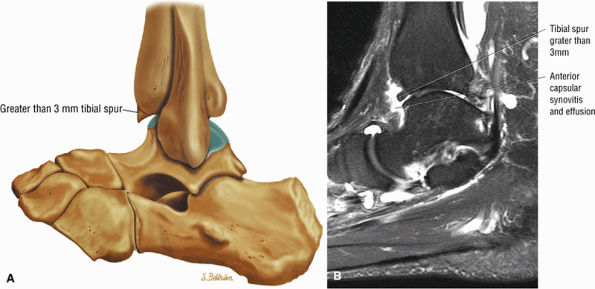

Anterior osseous impingement of the ankle with spurring of the anterior aspect of the tibiotalar joint and bone marrow edema demonstrated in the anterior distal tibia